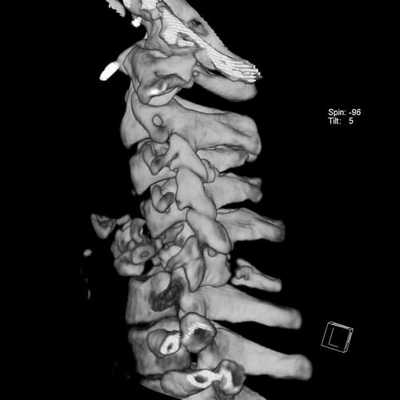

При наличии специального программного обеспечения для МРТ и клинической необходимости можно получить трехмерное изображение (в 3D) позвоночника и оценить структуру последнего комплексно. Рентген такой возможности не предоставляет.

КТ, в отличие от МРТ позвоночника, проводится с помощью небольшого количества рентгеновского излучения. По сути дела, компьютерный томограф - это улучшенный рентгеновский аппарат, позволяющий делать объемные снимки и рассматривать отдельные срезы исследуемой области. КТ наиболее эффективна при диагностике повреждений костных структур и кровотечений. Кроме того, компьютерная томография используется для диагностики сложных травм позвоночника и обследования полых внутренних органов в случаях, когда МРТ провести невозможно.

Отличия МРТ от КТ позвоночника

Основные отличия МРТ от КТ позвоночника кроются в принципе получения изображения. Современная компьютерная томография (или МСКТ - мультиспиральная компьютерная томография) основана на способности по-разному, в зависимости от плотности тканей, поглощать рентгеновское излучение. Особенности мультиспиральной компьютерной томографии позвоночника заключаются в том, что в ходе процедуры собираются множественные непрерывно перекрывающиеся срезы. Это дает возможность производить компьютерную обработку данных с последующим созданием объемных, так называемых 3D изображений и реконструкций. Полученные на МСКТ позвоночника снимки врачи могут рассматривать на экране с любой стороны как в режиме индивидуального просмотра, так и в режиме анимации, когда объект вращается вокруг своих осей. Используя специальные функции разворота и обрезки, можно выделить интересующую область и визуализировать ее с любой стороны. Это дает возможность медикам видеть скрытые структурные повреждения.

Перелом грудного отдела (трехмерная и сагиттальная проекции)

В результате компьютерной томографии получают серию послойных изображений рассматриваемой зоны. Монохромные фотографии обладают высоким разрешением. В отличие от рентгенографии на снимках отсутствуют дефекты и тени от расположенных рядом структур. Изменение плоскости при реконструкции изображений позволяет тщательно изучить анатомические образования. Преимуществом КТ является возможность создания 3D-модели позвоночника.

Трехмерная реконструкция при КТ